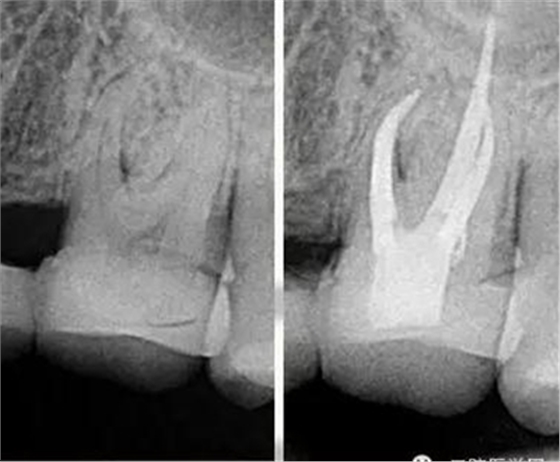

我喜歡比較有挑戰(zhàn)的工作,在牙科治療中最有挑戰(zhàn)的治療之一就是根管治療。牙齒的根管系統(tǒng)非常復(fù)雜,就像一顆大樹(shù),有主干也有枝葉,要把這么復(fù)雜的根管系統(tǒng)治療到位很有挑戰(zhàn)。它需要掌握的技術(shù)比較多,涉及到的器械是最多的,治療一顆牙常常需要擺出3大桌的工具。當(dāng)你花了很長(zhǎng)時(shí)間把一顆牙的根管治療治療到位以后,看著術(shù)后的X線片,感覺(jué)就像在欣賞一件藝術(shù)作品,非常美,非常有成就感。

把根管感染清理出來(lái),除了旋轉(zhuǎn)鎳鈦器械的切屑往外帶出來(lái)以外還有一些殘留的碎屑粘在根管壁上,要把這部分碎屑沖出來(lái),就會(huì)用到根管超聲器械或者聲波器械,通過(guò)高頻震動(dòng),帶動(dòng)根管內(nèi)部沖洗液的震動(dòng),從而讓那些殘留碎屑從根管壁上脫落下來(lái)并且被沖出來(lái)。好了,現(xiàn)在根管內(nèi)部都清理干凈了,剩下這個(gè)空腔我們要把它完全的填起來(lái),不讓外界的細(xì)菌進(jìn)入內(nèi)部。這個(gè)時(shí)候我們會(huì)用到一種材料叫牙膠,這種材料比較穩(wěn)定,可以長(zhǎng)期的存在根管里。現(xiàn)在比較先進(jìn)的牙膠充填是熱牙膠充填系統(tǒng),把牙膠加熱到一定溫度后具有流動(dòng)性,通過(guò)垂直加壓,讓它自動(dòng)的把整個(gè)根管系統(tǒng)都填滿。